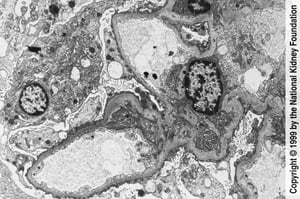

透過型電子顕微鏡下で足突起の広範な鈍化および消失が認められる(3000倍)。